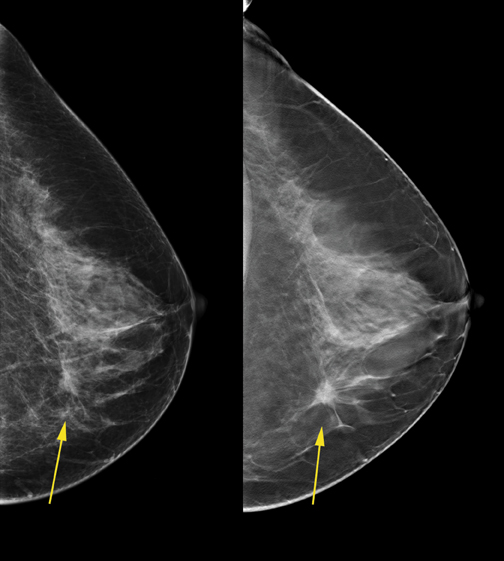

- Η HOLOGIC είναι η μόνη εταιρία που διαθέτει έγκριση από FDA σχετικά με την υπεροχή της συγκεκριμένης τεχνικής τομοσύνθεσης έναντι της κλασσικής 2D ψηφιακής μαστογραφίας και ειδικά για τις γυναίκες με πυκνούς μαστούς (FDA indication of equivalent/superior to FFDM).

Επισημαίνουμε ότι είναι εντελώς διαφορετικό να αναγράφεται στην κλινική ένδειξη FDA του εκάστοτε μηχανήματος (Physician Labelling) ότι η τεχνολογία τομοσύνθεσης προορίζεται για την ίδια κλινική εφαρμογή με την συμβατική ψηφιακή μαστογραφία και εντελώς διαφορετικό να αναγράφεται ότι η συγκεκριμένη τεχνολογία τομοσύνθεσης προορίζεται να παρέχει μια ανώτερη κλινικά εξέταση με μεγαλύτερη διαγνωστική ακρίβεια συγκριτικά με την 2D μαστογραφία και ειδικά για τους πυκνούς μαστούς , όπως μόνο στον SELENIA DIMENSIONS.

Ο ψηφιακός μαστογράφος ΤΟΜΟΣΥΝΘΕΣΗΣ που λειτουργεί στο κέντρο μαστού είναι ο μοναδικός με τη χρήση του οποίου έχει αποδειχθεί από πολυάριθμες ανεξάρτητες πολυκεντρικές κλινικές μελέτες ότι εξασφαλίζεται αύξηση της διαγνωστικής ευαισθησίας και ειδικότητας της εξέτασης μαστογραφίας, αύξηση ανίχνευσης των αληθώς καρκινικών ευρημάτων και ταυτόχρονη μείωση των ψευδώς υπόπτων ευρημάτων.

Ειδικότερα από τουλάχιστον 200 δημοσιευμένες κλινικές μελέτες (π.χ. OSLO Breast Screening Trial), προέκυψε ότι με την χρήση του Ψηφιακού Μαστογράφου SELENIA DIMENSIONS 3D για τον συνδυασμό 2D και 3D ψηφιακής μαστογραφίας εξασφαλίζεται:

- 20-65% αύξηση στην ανίχνευση των διηθητικών καρκίνων

- 27% αύξηση στην ανίχνευση καρκίνων (διηθητικών και μη διηθητικών)

- 15% μείωση σε ψευδώς θετικά αποτελέσματα